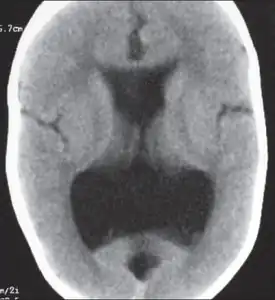

Colpocephaly is characterized by disproportionately large occipital horns of the lateral ventricles (also frontal and temporal ventricles in some cases). MRI and CT scans of patients demonstrate abnormally thick gray matter with thin poorly myelinated white matter. This happens as a result of partial or complete absence of the corpus callosum. Corpus callosum is the band of white matter connecting the two cerebral hemispheres. The corpus callosum plays an extremely important role in interhemispheric communication, thus lack of or absence of these neural fibers results in a number of disabilities.[12]

Image indicates colpocephaly with septal agenesis -

After birth, MR imaging can be done to look for cephalic abnormalities. This is the most commonly used method for diagnosing colpocephaly. Physicians look for abnormally large occipital horns of the lateral ventricles and diminished thickness of white matter.[12] Spinal tapping is not a preferred method for diagnosis because newborn babies with colpocephaly or hydrocephaly have open fontanelles which makes it difficult to collect CSF. Also, colpocephaly is not associated with increased pressure.[13]